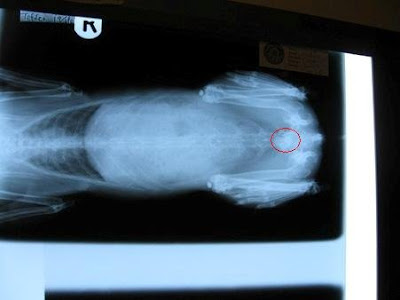

由於我已用試紙確認為血尿,獸醫Dr. Jaime先替他照x-ray,

x-ray顯示有一粒體積較大的結石在膀胱,並安排隔天進行手術